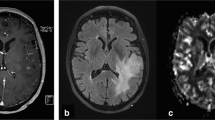

Imaging studies were obtained using a 1.5-T Signa MR scanner (General Electric Medical Systems). The MR imaging protocol consisted of T1-weighted spin-echo (SE) sagittal sections (400/14 TR/TE), axial fluid attenuated inversion recovery (FLAIR 8802/142/2200 TR/TE/TI), axial fast spin-echo (FSE) T2-weighted imaging (4360/102 TR/TE), 2D dynamic susceptibility-weighted, SE, echoplanar imaging (EPI 1900/80 ms, bandwidth 62.5) and postcontrast T1-weighted SE (600/14 TR/TE) or FLAIR (2280/11/750 TR/TE/TI) axial imaging. The T2-weighted FLAIR, FSE and postcontrast T1-weighted images were used to define regions of T2 hyperintensity and T1 enhancement. For the dynamic EPI series, the tumour size and location, and the position of the margins were determined from the T2-weighted FLAIR or FSE images to equally define low-grade and high-grade tumours. Nine slices were selected to cover the majority of the tumour volume. Slice thickness was 7 mm, with no gap. A standard dose of 0.1 mmol/kg body weight of dimeglumine gadopentetate (Gd DTPA) was injected intravenously manually at an approximate rate of 3 ml/s. A series of T2*-weighted multislice image sets (field of view 30×30, matrix 192×128) were acquired every 2 s during the first pass of the contrast agent. Image postprocessing was performed using commercial software (Functool2, version 6.0; Sun Microsystems). Negative enhancement integral (NEI) maps were generated for each patient relative to the signal intensity in the superior sagittal sinus (Fig. 1). The axial slice with the greatest cerebral blood volume and tumour area was chosen for analysis.

Calculation of rCBV using DSC-MR. CBV is derived from the drop in the T2* signal after injection of a bolus of paramagnetic compound [8, 9]. Using Functool2, the radiological tumour margin was delineated on the T2* sequence axial image and a single circular ROI placed over normal brain mirrored in the contralateral hemisphere (a, b). Negative enhancement integral (NEI) colour maps were generated (c, d) relative to the signal intensity in the superior sagittal sinus using image data between dynamic scans immediately before and after the contrast transient. CBV is proportional to the area under the contrast agent concentration-time curve and was calculated for each ROI by Functool2 using algorithms to integrate ΔR2i values (where ΔR2 is the change in the reciprocal of T2*). rCBV for each tumour was calculated from signal intensity time curves for individual ROIs placed within the delineated tumour region or in the large ROI in the contralateral hemisphere (as illustrated in e and f, arrows scans adjacent to the contrast transient) as described in the Materials and methods. a, c, e Low rCBV (0.73±0.17, mean±SD) in a grade II oligoastrocytoma with intact chromosomes 1p and 19q and; b, d, f high rCBV (4.15±0.87) in a grade II oligoastrocytoma with the −1p/−19q genotype

The radiological tumour margin was delineated on the T2* sequence axial image using a nongeometric region of interest (ROI), and a single circular region was placed over normal brain mirrored in the contralateral hemisphere. Depending on tumour location, the mirrored area could include both white and grey matter. ROIs were placed according to published methods giving the lowest inter- and intraobserver variability [20] within the delineated tumour region. Briefly, five ROIs (area range 12–27 mm2) were placed over the tumour areas with the highest blood volume. Cystic and hemorrhagic regions were avoided and care was taken not to place ROIs over normal blood vessels or a biopsy tract where seen. Three independent analyses were performed by a neuroradiologist (T.S.S.) and a neurosurgeon (M.D.J.) blinded to histology and genotype, to assess inter- and intraobserver variability. For each observation, data were expressed relative to the internal reference (four ROIs placed within the delineated mirrored region of normal brain without deliberate bias towards either grey or white matter) to generate relative cerebral blood volume (rCBV) values (mean ROItumour/mean ROInormal brain) and accommodate physiological differences between patients [21]. For comparison with clinical data, the mean rCBV from these three data sets was used.

Tumour rCBV was obtained from DSC-MRI (Fig. 1) by two independent observers. Bland and Altman plots revealed low inter- and intraobserver variation (Fig. 2). The closest observed limits of agreement were between the first observations of the neuroradiologist and neurosurgeon (mean −0.17, range −1.27 to 0.93; Fig. 2a). The widest observed limits of agreement were between the repeat observations of the neurosurgeon (mean 0.08, range −1.59 to 1.95; Fig. 2c). The greatest variation was observed in tumours with higher rCBV values.